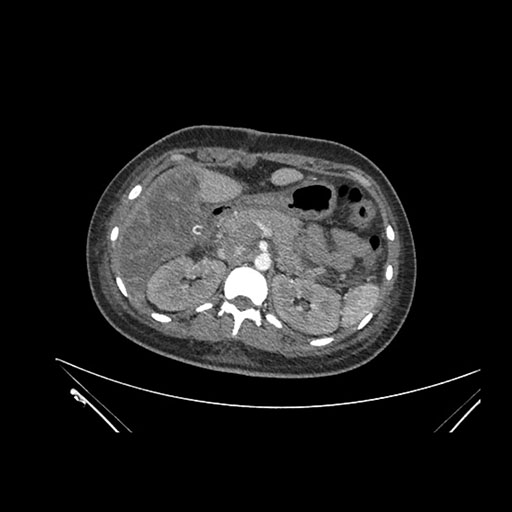

Axial Arterial

Imaging analysis

Based on initial findings, which issue(s) would you be most concerned about?